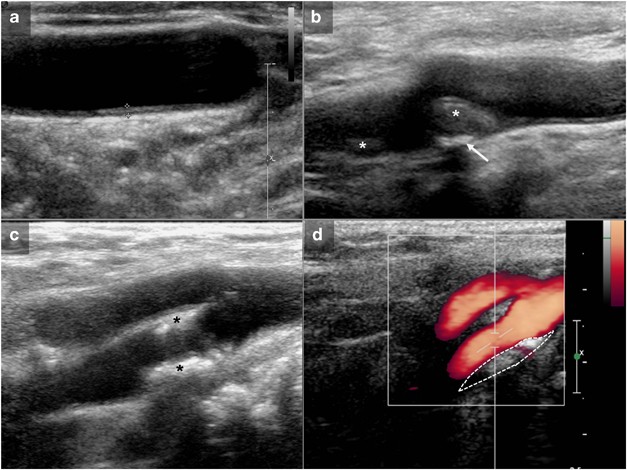

Carotid Doppler ultrasonography was carried out by two neuroradiologists (JMGS, STR) with 20 and 9 years of experience, respectively, using the same protocol and ultrasound equipment (Esaote Technos MPX, Genoa, Italy). Two intima-media thickness measurements were carried out at the distant wall of each common carotid artery, one at the mid-third of the artery and the other just proximal to the carotid division, always at the widest point of the wall (Figure 3). The two measurements were averaged to give an overall thickness. The presence of carotid plaques was reported and classified as mainly soft or mainly calcified when soft or calcium components, respectively, were undoubtedly dominant from a visual point of view (Figure 3). When both types of plaques appeared in the same patient, it was classified as a mixture of plaques. Doubtful cases were decided by consensus between the two raters. Peak systolic and diastolic velocities were obtained in the common carotid artery, close to the carotid division, and in the internal carotid artery, immediately distal to the carotid bulb or at the level of a plaque-related lumen stenosis (Figure 3), with the Doppler box in the middle of the arterial lumen, always with the same size and at an angle of 60°. Systolic and diastolic internal carotid artery to common carotid artery ratios were automatically calculated and were used for analysis.

(a) Intima-media thickness measurement at the level of the mid stretch of the common carotid artery. Measurements were always carried out between the free edge of the intima and the transition from the hypoechogenic intima-media complex to the echogenic adventitia, and averaged with the same measurement in the distal common carotid artery. (b) Mainly soft carotid plaques (stars), one of them (arrow) with a nondominant calcification. (c) Mainly calcified internal carotid plaques (stars). (d) Internal carotid measurements were carried out just distal to the carotid bulb unless a plaque-related lumen narrowing was detected. In that case, flow velocities were acquired at the level of the stenosis. Dashed line: calcified plaque.